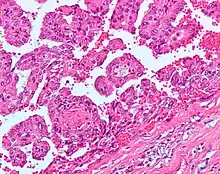

Papillary Renal Cell Carcinoma (PRCC)

Type 1 PRCC consist of papillae covered with a single or double layer of small cuboid cells with scanty cytoplasm and Type 2 PRCC consist of papillae covered by large eosinophilic cells arranged in an irregular or pseudostratified manner. |

Histopathology

The gross and microscopic appearance of renal cell carcinomas is highly variable. The renal cell carcinoma may present reddened areas where blood vessels have bled, and cysts containing watery fluids.[58] The body of the tumour shows large blood vessels that have walls composed of cancerous cells. Gross examination often shows a yellowish, multilobulated tumor in the renal cortex, which frequently contains zones of necrosis, haemorrhage and scarring. In a microscopic context, there are four major histologic subtypes of renal cell cancer: clear cell (conventional RCC, 75%), papillary (15%), chromophobic (5%), and collecting duct (2%). Sarcomatoid changes (morphology and patterns of IHC that mimic sarcoma, spindle cells) can be observed within any RCC subtype and are associated with more aggressive clinical course and worse prognosis. Under light microscopy, these tumour cells can exhibit papillae, tubules or nests, and are quite large, atypical, and polygonal.